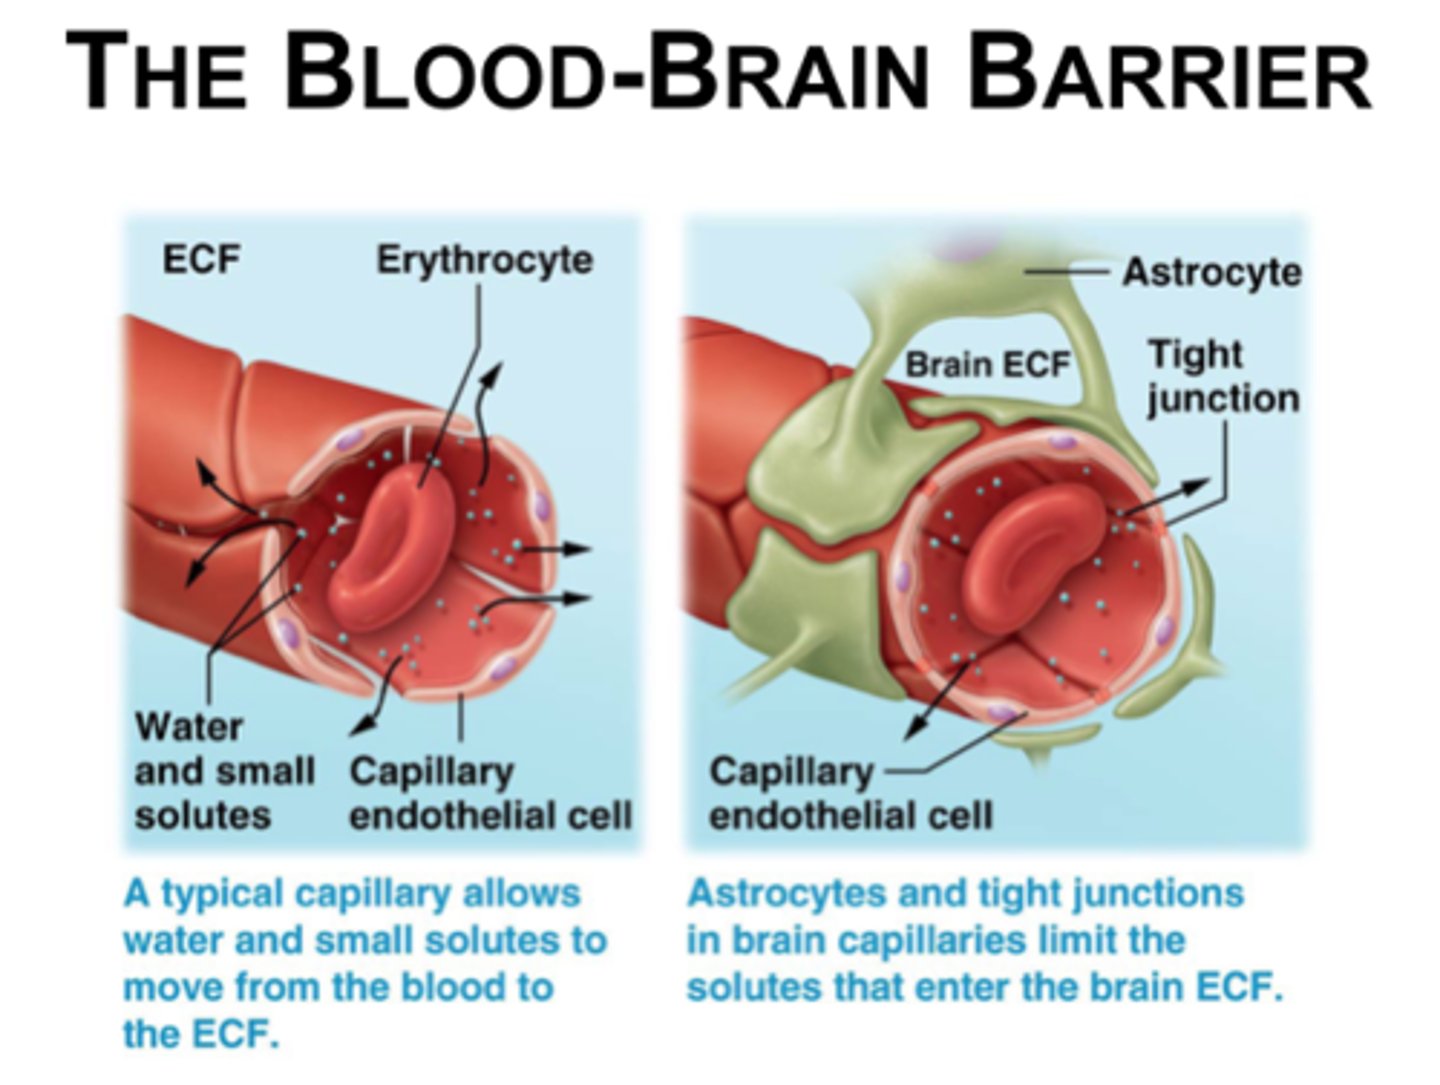

Blood Brain Barrier

Tight junctions between endothelial blood vessel cells cause substances to pass through cells to become Cerebrospinal fluid (CSF),

Not completely uniform in all areas

Blood brain barrier and tight junction/ substances becoming CSF

1) Large substances/molecules cannot utilize the route between cells and are barred from CSF.

2) Lipid-soluble substances, such as nicotine, ethanol, and heroin, can diffuse through the endothelial cell membranes and enter the brain.

3) Water-soluble molecules such as amino acids and glucose move across by mediated transport

Blood brain barrier not completely uniform in all areas:

1) Very permeable in vomiting venter in brain stem

- allows monitoring of blood for poisonous substances

2) Very permeable in hypothalamus

- allows sampling of chemical composition of blood to regulate water balance, body temp, etc.